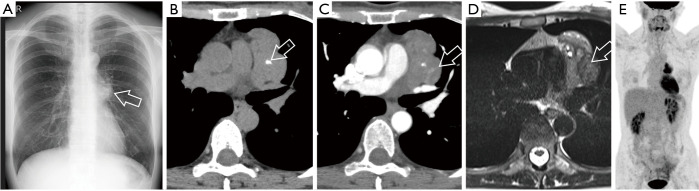

这篇综述文章全面探讨了胸腺上皮性肿瘤 (TET) 和其他纵隔肿块的诊断方法,重点是成像模式和鉴别诊断。文章首先讨论了纵隔肿瘤的传统和现代分类系统,包括日本胸腺研究协会(JART)和国际胸腺兴趣小组(ITMIG)的分类,然后强调了向基于计算机断层扫描(CT)分类的转变。重点强调了区分前纵隔实性和囊性病变的重要性,并详细介绍了胸腺瘤、胸腺癌和胸腺神经内分泌肿瘤(NET)等各种 TET 亚型的影像学特征和组织学特征。该综述还阐明了常见的鉴别诊断,包括淋巴瘤和生殖细胞瘤,为准确诊断的关键影像学发现和注意事项提供了指导。此外,书中还强调了患者背景和血液检查在鉴别诊断中的重要性,并讨论了与年龄相关的发病模式和肿瘤标志物评估。在探讨了胸腺囊肿给诊断带来的挑战,对其放射学特征、管理注意事项和潜在并发症提出见解后,本综述扩展到其他罕见纵隔病变,强调了对这些肿瘤进行准确识别和管理的全面评估的必要性。最后,作为示例,我们介绍了六个病例,着重说明包括 TET 在内的前纵隔肿瘤的各个方面。这些病例为临床实践中遇到的诊断难题、影像学特征和管理注意事项提供了宝贵的见解。本文介绍的病例并不都是典型的图像、病程和诊断。但是,每个病例都具有重要意义。因此,我们在介绍这些病例时,相信它们有助于理解实际临床实践中影像诊断的复杂细微差别。

This review article comprehensively examines the diagnostic approach to thymic epithelial tumors (TETs) and other mediastinal masses, focusing on imaging modalities and differential diagnosis. Beginning with a discussion on traditional and contemporary classification systems for mediastinal tumors, including the Japanese Association for Research on the Thymus (JART) and International Thymic Interest Group (ITMIG) classifications, it highlights the shift towards computed tomography (CT)-based categorizations. Emphasis is placed on the importance of distinguishing between solid and cystic lesions in the anterior mediastinum, with detailed insights into imaging characteristics and histological features of various TET subtypes such as thymomas, thymic carcinomas, and thymic neuroendocrine tumors (NETs). The review also elucidates common differential diagnoses, including lymphomas and germ cell tumors, providing guidance on key imaging findings and considerations for accurate diagnosis. Furthermore, it underscores the significance of patient background and blood tests in differential diagnosis, discussing age-related prevalence patterns and tumor marker assessment. After addressing the diagnostic challenges posed by thymic cysts offering insights into their radiological features, management considerations, and potential complications, this review extends to other rare mediastinal lesions highlighting the need for a comprehensive evaluation for accurate identification and management of these tumors. Finally, as illustrative examples, we present six cases highlighting various aspects of anterior mediastinal tumors, including TET. These cases provide valuable insights into the diagnostic challenges, imaging characteristics, and management considerations encountered in clinical practice. The cases presented herein do not all illustrate typical images, courses, and diagnoses. However, they each contain significant implications. Thus, we present them with the belief that they will aid in understanding the intricate nuances of image diagnosis in actual clinical practice.